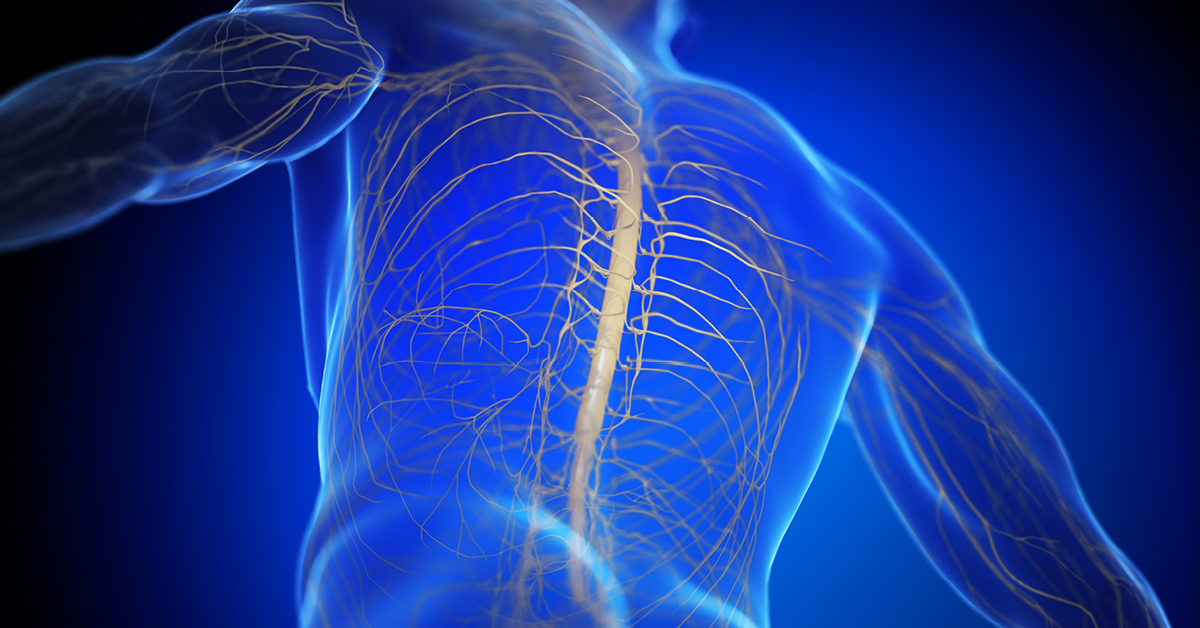

Cauda Equina Syndrome (CES) is a very rare but serious condition, where the bundle of nerves called the Cauda Equina at the bottom of the spine get compressed. The Cauda Equina control the function of the bladder and bowel, and the sensation to the skin of the genitals and bottom area. CES most commonly results from a massive herniated disc in the lumbar region but can also be caused by spinal lesions and tumours, spinal infections or inflammation and other less common conditions.